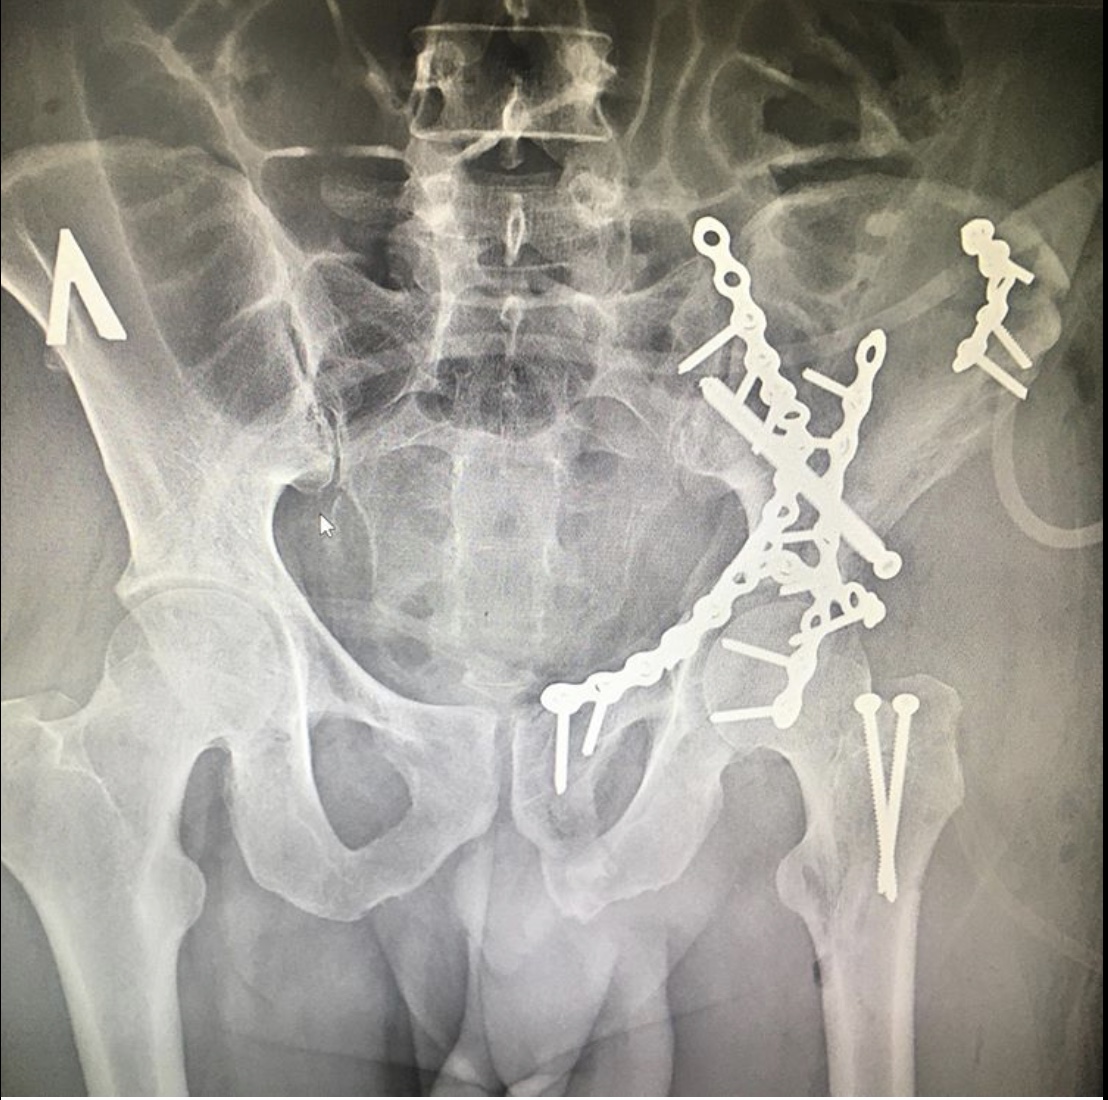

Как рассказал хирург – травматолог – ортопед ГКБ 7 Казани Руслан Ильгизарович Закиров, после стабилизации гемодинамических показателей был выполнен остеосинтез реконструктивными пластинами и винтами. При такой травме вероятность «выживания» тазобедренного сустава очень невелика. Но при любом развитии ситуации созданы условия для дальнейшего лечения и реабилитации пациента.